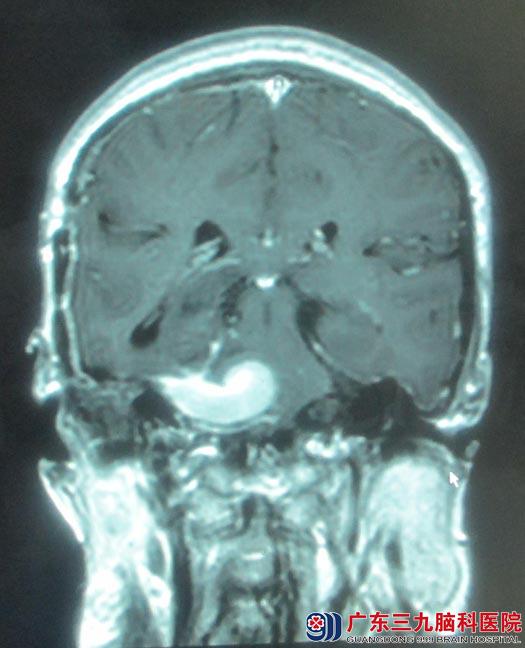

入住广东三九脑科医院综合神经外科时查体:声音嘶哑,右耳失聪,右侧眼睑抬举无力,右眼外展不能到边,右侧面部痛温觉减退,角膜反射迟钝;右侧额纹、鼻唇沟变浅,舌前2/3味觉减退,饮水呛咳,吞咽困难,右侧软腭运动减弱,悬雍垂偏右,右侧咽反射消失,右侧转头颈、耸肩较左侧差,伸舌偏右,四肢肌力:左侧4级,右侧5级,轻瘫试验阳性。头颅MR检查提示“右侧中后颅窝占位,大小约4 cm×3cm,考虑脑膜瘤”,

鲁明主任阅片后认为:右侧中后颅窝、延斜区脑膜瘤,目前已对动眼神经、外展神经、三叉神经、面听神经、舌咽神经及副神经造成影响,并与脑干紧密相连,手术风险大。经过周全安排,由鲁明主任主刀,术中取右侧乙状窦后入路,见肿瘤呈灰白色,边界较清,质中,血供丰富。肿瘤供血主要由延斜区硬脑膜动脉参与,岩上窦与肿瘤关系密切,予显微镜下电凝烧灼分离肿瘤基底部供血动脉,分块切除肿瘤。过程中岩上窦及海绵窦均有出血,予明胶海绵压迫止血,肿瘤边缘近包膜区,面听神经、三叉神经、迷走神经、副神经及舌咽神经粘连紧密,在电生理监测下,仔细辨认,小心分离,中后组颅神经均解剖保留,肿瘤内侧面与脑干粘连紧密,为避免脑干损伤导致术后严重功能障碍,予残留部分肿瘤。术中出血少,术后恢复良好,病理结果示:纤维型脑膜瘤(WHO1级)。

手术前